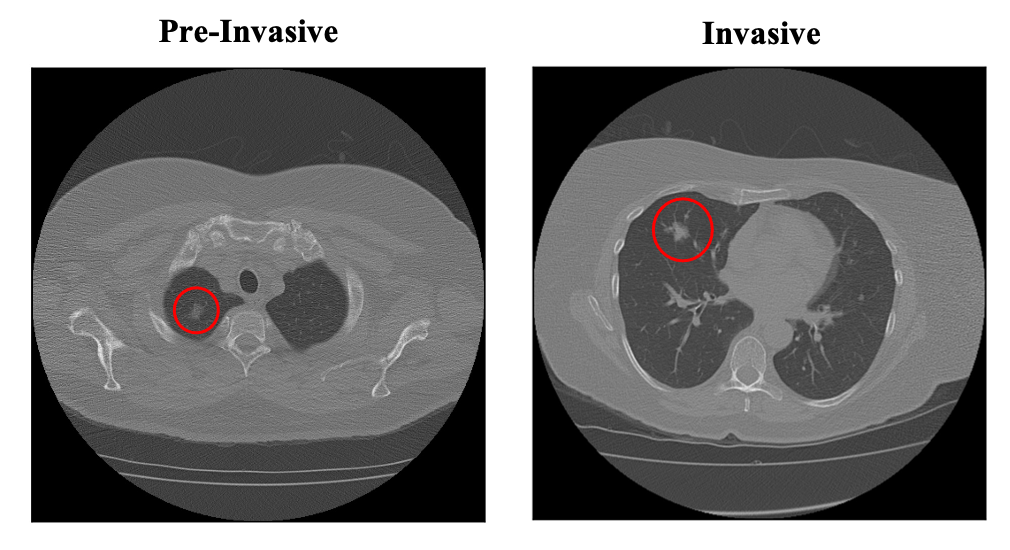

Lung cancer is the leading cause of mortality from cancer worldwide and has various histologic types, among which Lung Adenocarcinoma (LUAC) has recently been the most prevalent. Lung adenocarcinomas are classified as pre invasive, minimally invasive, and invasive adenocarcinomas. Timely and accurate knowledge of the invasiveness of lung nodules leads to a proper treatment plan and reduces the risk of unnecessary or late surgeries. Currently, the primary imaging modality to assess and predict the invasiveness of LUACs is the chest CT. The results based on CT images, however, are subjective and suffer from a low accuracy compared to the ground truth pathological reviews provided after surgical resections. In this paper, a predictive transformer-based framework, referred to as the "CAE-Transformer", is developed to classify LUACs. The CAE-Transformer utilizes a Convolutional Auto-Encoder (CAE) to automatically extract informative features from CT slices, which are then fed to a modified transformer model to capture global inter-slice relations. Experimental results on our in-house dataset of 114 pathologically proven Sub Solid Nodules (SSNs) demonstrate the superiority of the CAE-Transformer over the histogram/radiomics-based models and its deep learning-based counterparts, achieving an accuracy of 87.73%, sensitivity of 88.67%, specificity of 86.33%, and AUC of 0.913, using a 10-fold cross-validation.